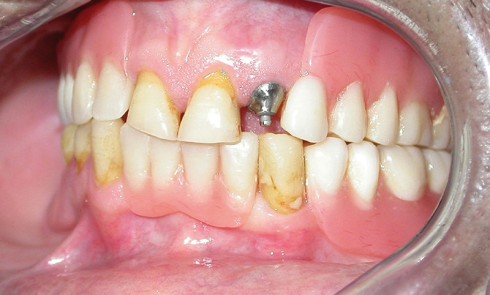

Article réservé à nos abonnés La prothèse composite dans la gestion esthétique et biomécanique d’un édentement unilatéral de grande étendue

La réhabilitation des édentements terminaux unilatéraux de grande étendue par prothèse amovible partielle métallique (PAPIM) conventionnelle pose plusieurs problèmes essentiellement...